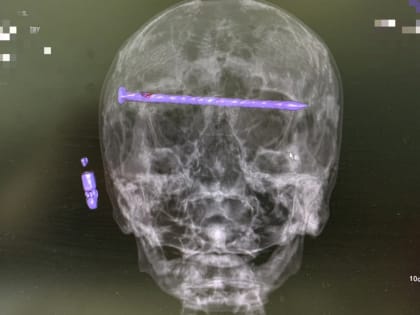

Тагильские нейрохирурги спасли жизнь мужчине, у которого в черепе был 15-сантиметровый гвоздь

В городской больнице № 1 Нижнего Тагила нейрохирурги провели сложную операцию по извлечению 15-сантиметрового гвоздя из черепа 78-летнего пациента, сохранив ему жизнь и зрение,